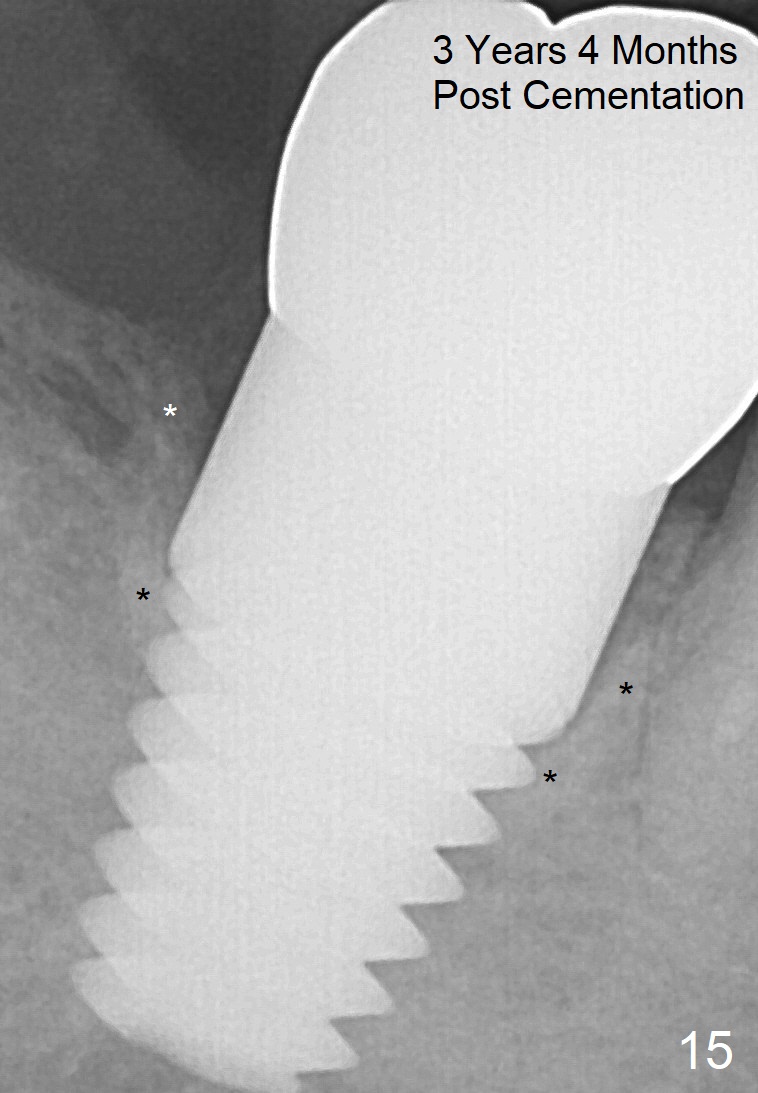

The lamina dura-like dense bone forms coronally 3 years 4 months post cementation (Fig.15 *).